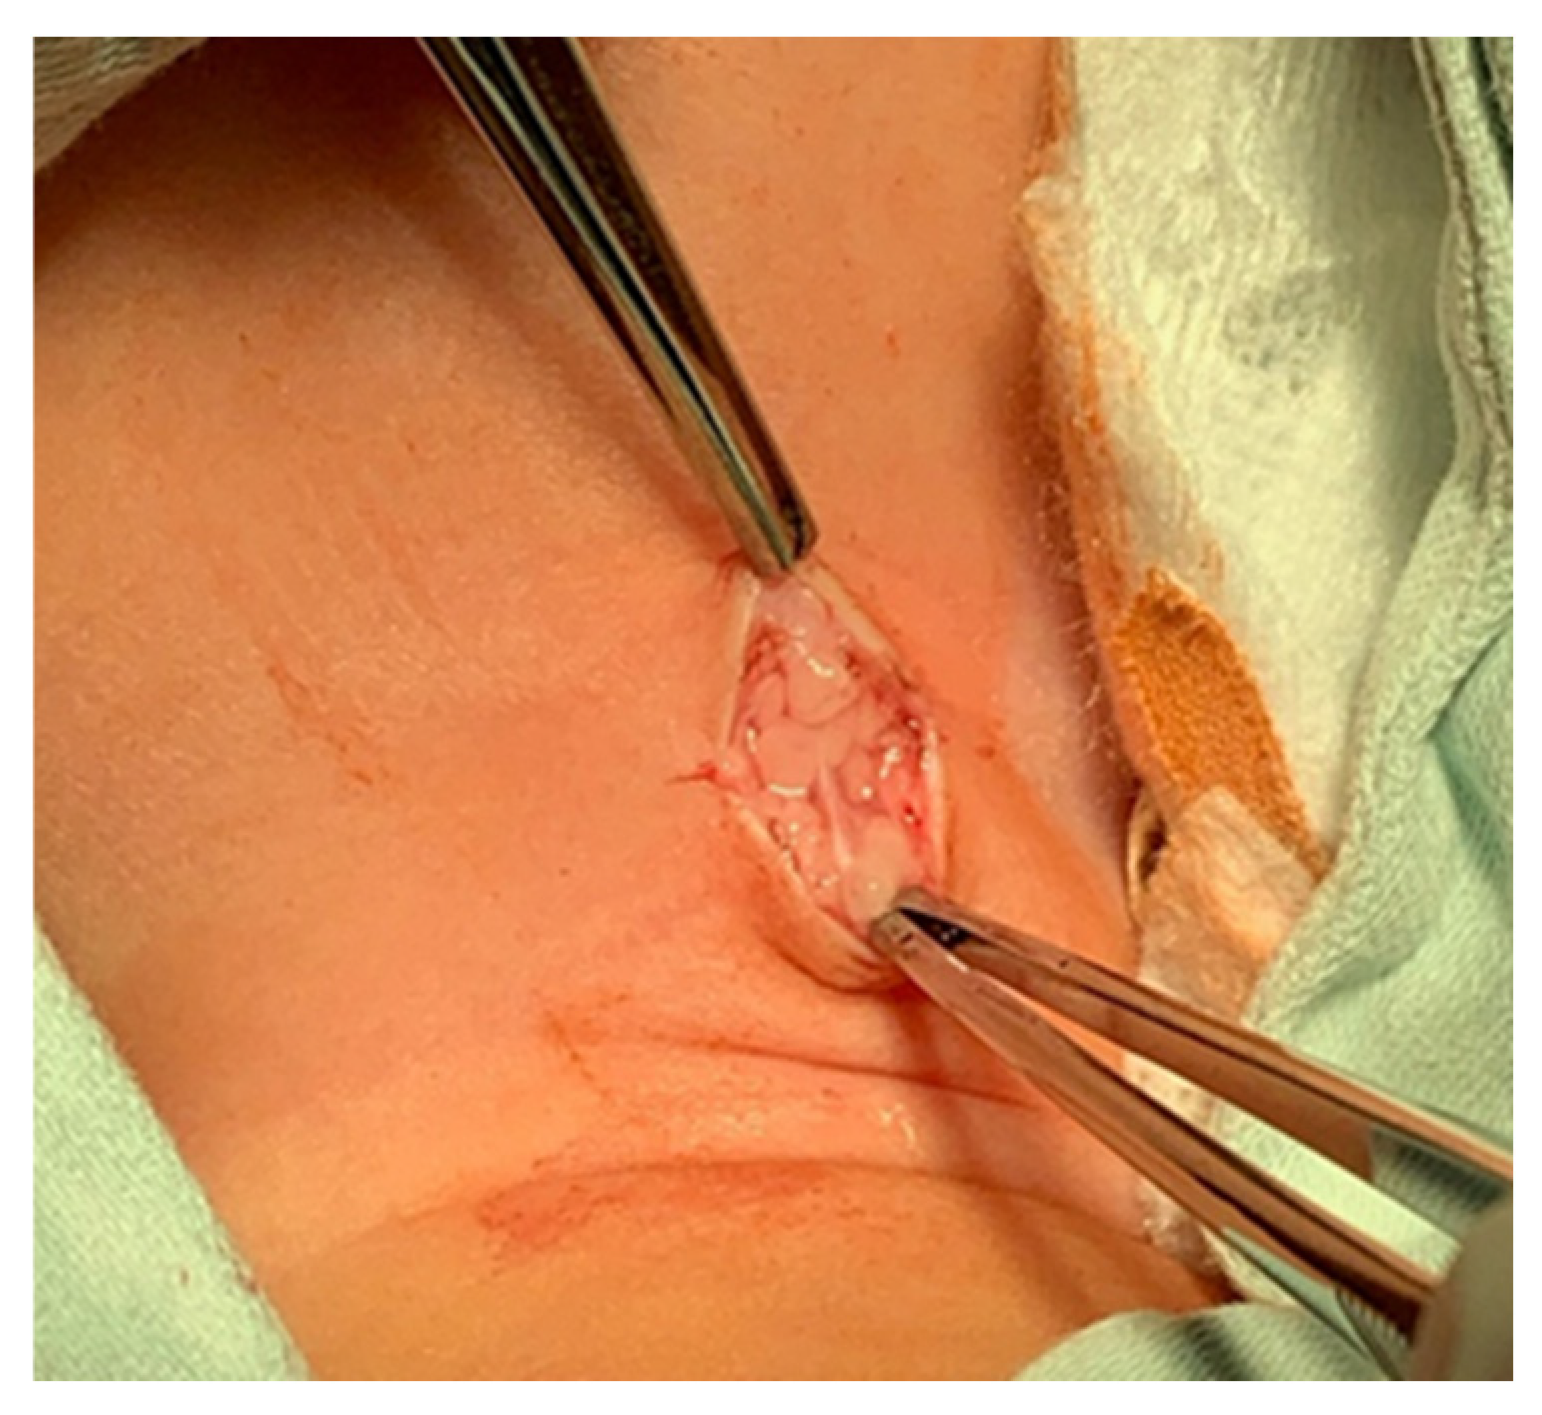

- A midline incision is made on the neck, halfway between the cricoid cartilage and the jugular notch (Figure 1). The incision can be either horizontal or vertical, with a horizontal incision being used in most cases.

- The subcutaneous tissue is carefully dissected (Figure 2).